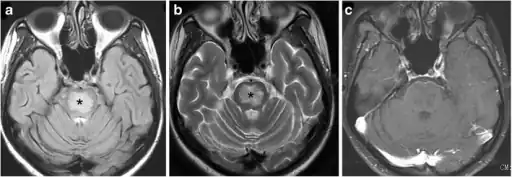

a-c)Individual with electrolyte imbalance and altered sensorium

Electrolytes are important because they are what cells (especially nerve, heart and muscle cells) use to maintain voltages across their cell membranes. Electrolytes have different functions, and an important one is to carry electrical impulses between cells. Kidneys work to keep the electrolyte concentrations in blood constant despite changes in the body.[5][7] For example, during heavy exercise, electrolytes are lost in sweat, particularly in the form of sodium and potassium.[7] The kidneys can also generate dilute urine to balance sodium levels.[7] These electrolytes must be replaced to keep the electrolyte concentrations of the body fluids constant. Hyponatremia, or low sodium, is the most commonly seen type of electrolyte imbalance.[8][9]